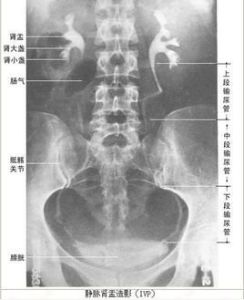

排泄性尿路造影(excretory urography)又稱靜脈腎盂造影(intravenous pyelography,以下稱IVP),泌尿系疾病的診斷中是最常用且有效的檢查方法之一。 它是將造影劑注入靜脈後,幾乎全部以原形經過腎小球,腎小管濃縮排出使之顯影,不但可以顯示腎盂腎盞、輸尿管及膀胱內腔解剖形態,而且可以了解兩腎的排泄功能。

1-2min腎實質顯影,2-3min腎盂、腎盞開始顯影。15-30min腎盂、腎盞顯影最濃。

仰臥位,成人60%的泛影葡胺20ml肘靜脈注射,下腹加壓阻斷。